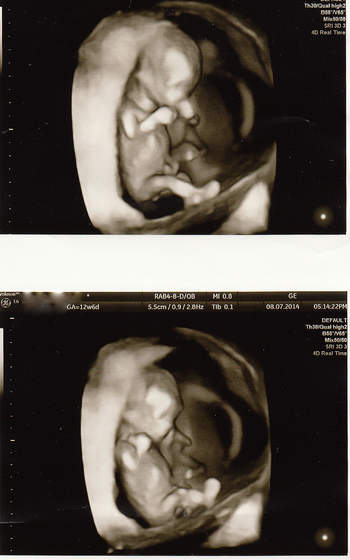

Hej ja po wizycie, bąbel młodszy o 2 dni niz z OM wiec mam sie za tydz pokazac na przeziernosc. Reszta ok, raczki, nozki, zoladek itd itd. Maluch ma 4,84 cm. Ja w pt ide na dokladne usg to moze cosik sie uda podgladnac a na razie taka tylko fotka na szybko. Tak sie wiercil maluch ze nie mozna bylo zrobic ladnego zdjecia